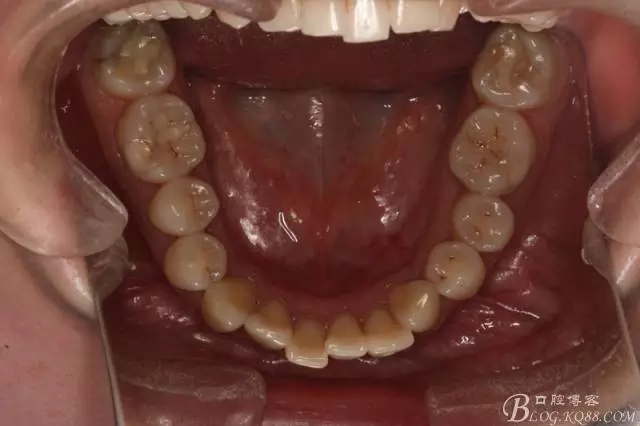

患者,女,主訴:牙齒不齊。

如圖,該病例為簡單排齊病例,但77鎖合是矯治中的關(guān)鍵所在,你會(huì)怎么處理?

該病例主要為17、27頰側(cè)位同時(shí)伴有伸長,當(dāng)然種植支抗可以解決,但還有簡單實(shí)用的辦法嗎?如圖,在橫腭桿遠(yuǎn)中延伸出牽引鉤,位置盡量遠(yuǎn)離合平面,7粘舌側(cè)扣,牽引力的方向?yàn)閴旱图吧嘞?,下圖為兩個(gè)月的效果,17已到位,27還未到位。